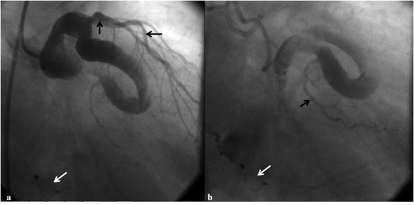

Figure 4. Immediate postprocedural coronary angiogram. Right anterior oblique cranial projection showed the device in situ (white arrows) without any residual shunt and normally filling branches of the left circumflex artery in the early (A) and late phase (B) (click thumbnail to view larger image).

After deployment, the left coronary angiography revealed complete closure of the defect as well as improved filling of the coronary branches (Figures 4A and 4B, Video 2). The procedure lasted for 30 minutes and fluoroscopy time was 8 minutes. The patient had an uneventful hospital course. There were no new changes in the daily electrocardiogram or serial rise of cardiac enzymes. The patient was discharged on aspirin and acinocoumarol, maintaining the therapeutic international normalized ratio (INR) between 2-2.5.